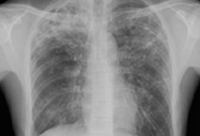

Chest x-ray showing increased opacification of the right perihilar region and superior segment of the right lower and upper lobes consistent with worsening aspiration pneumonia

From the personal collection of Dr R. Kanner, University of Utah School of Medicine